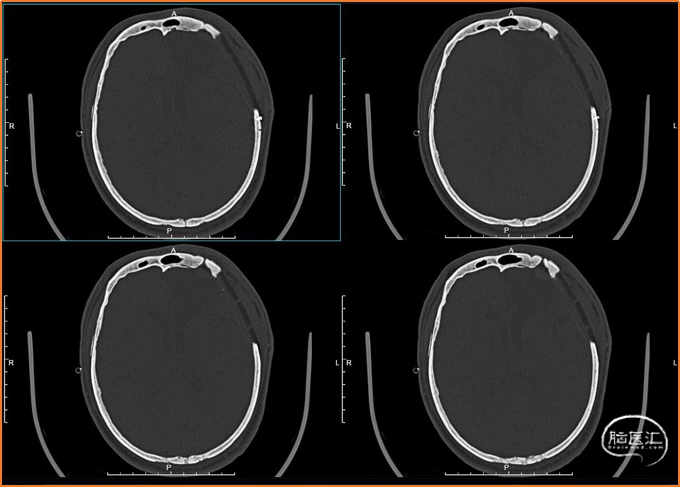

术前检查

手术过程

可见角突处钛网凹陷,皮瓣状况良好。